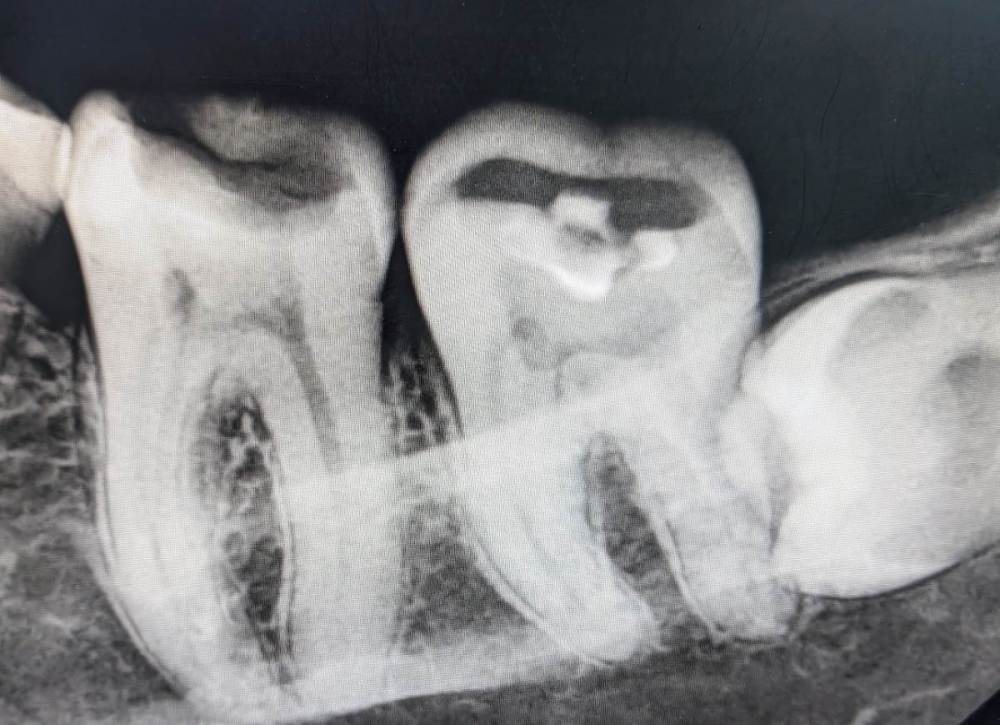

Govanna Опубликовано 23 января, 2024 Автор Поделиться Опубликовано 23 января, 2024 Врач который удалил в платной клинике, сказал все в порядке, пошла к другому- говорит гной, завтра заканчиваю пить антибиотики, а отек все ещё сильный. Посмотрите, пожалуйста, на снимке все в порядке? Действительно ли правильно так выпиливать? Ссылка на комментарий

Женька Опубликовано 23 января, 2024 Поделиться Опубликовано 23 января, 2024 @Govanna по этому снимку видно, что коронковая часть зуба точно отсутствует, не более того. 1 Ссылка на комментарий